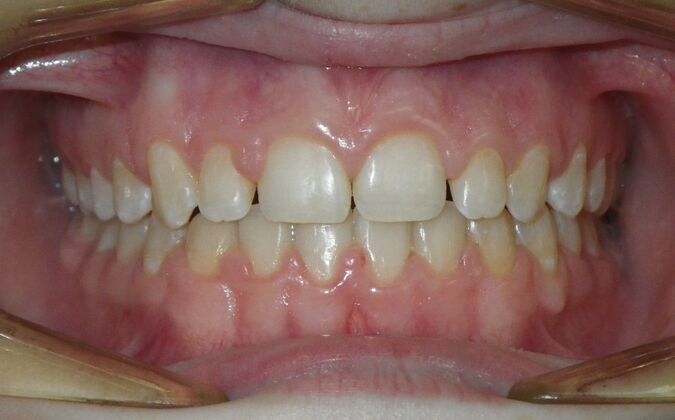

Patient presents desiring all spaces on upper and lower teeth closed. She will need slight expansion of upper arch due to lower molars leaning inward toward tongue. Used nitanium palatal expander with built in rotation of upper molars and lower lip bumper to upright lower first molars. Patient was also informed that her upper lateral incisors would require bonding due to their small size to close all space.